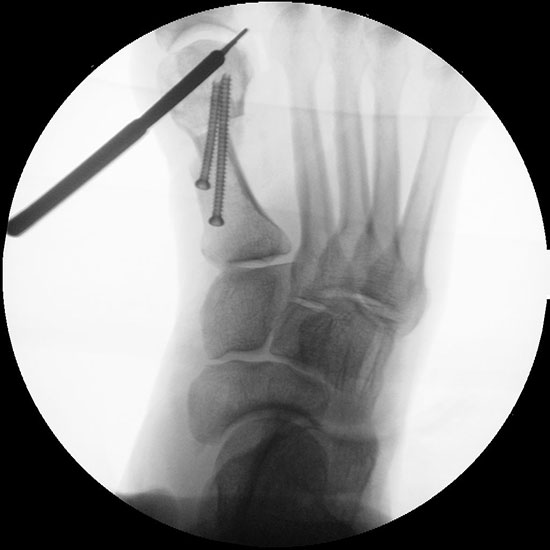

Abbildung 1

• Korrekturpotential größer als beim offenen Chevron, da die Gelenkkapsel als stabilisierendes Element erhalten bleibt und über eine trikortikale Osteosynthese mit zwei kanülierten Schrauben eine Verschiebung bis ca. 80% des Metatarsaledurchmessers möglich ist (Abb. 1).